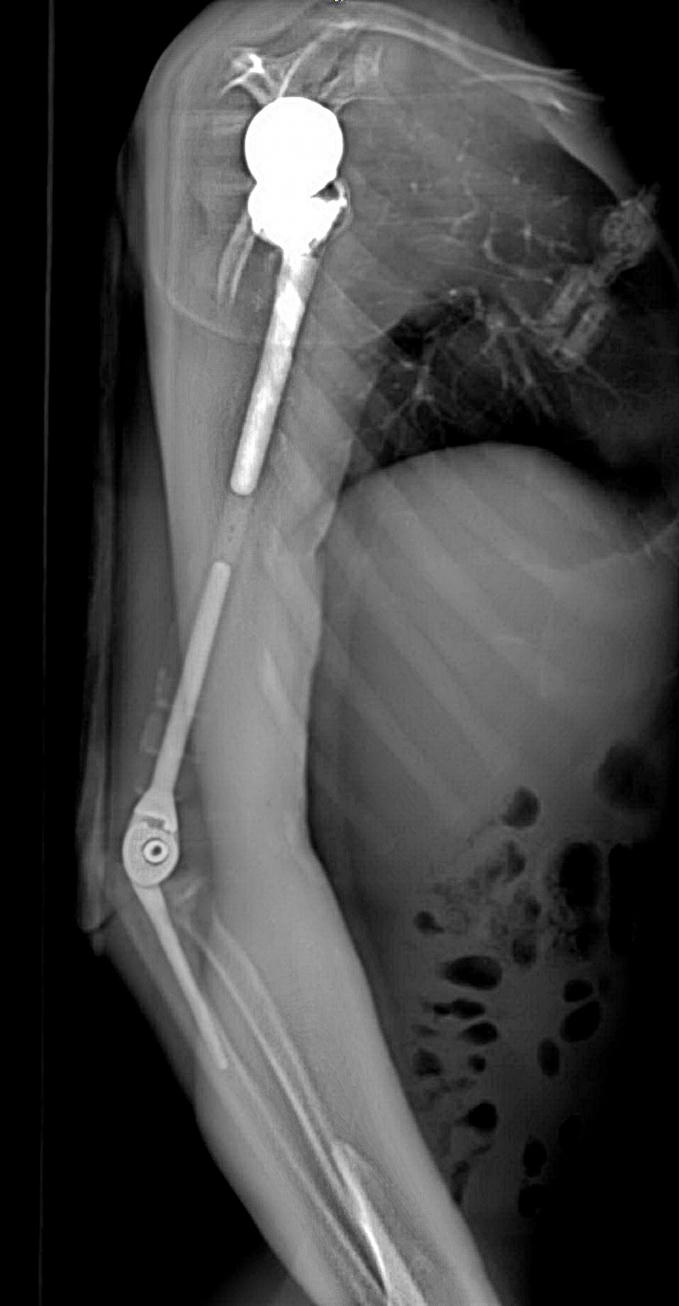

Nhóm phẫu thuật đã lên kế hoạch sử dụng các công nghệ trong tái tạo xương hiện đại nhất hiện nay bao gồm tái tạo lại cấu trúc khớp vai, cấu trúc khớp khuỷu bằng vật liệu hợp kim titan. Đặc biệt, đội ngũ bác sĩ của Trung tâm đã có một quyết định định táo bạo: không sử dụng hoàn toàn vật liệu kim loại mà chế tạo phần thân xương cánh tay sử dụng công nghệ in 3D vật liệu polyme sinh học (PEEK). Vật liệu này do phòng nghiên cứu ứng dụng công nghệ in 3D của Đại học VinUni sản xuất, giúp kết nối phần khớp vai và khớp khuỷu với nhau, đồng thời phục hồi lại điểm bám của các gân cơ quanh cánh tay. Đây được coi là một quyết định đầy tính sáng tạo dựa trên những nghiên cứu và thử nghiệm chuyên sâu từ nhiều ca bệnh đã thành công của ê-kíp phẫu thuật.

Đặc biệt, công nghệ in 3D được coi là công nghệ duy nhất hiện nay mang lại khả năng cá thể hóa các chi tiết cấy ghép. Nhờ công nghệ này, cả 3 phần của xương cánh tay nhân tạo đều được “thiết kế riêng” theo đúng kích thước cánh tay thật của bệnh nhân, đồng thời có các điểm cố định giúp khôi phục lại hệ thống gân cơ bám xương. Trước khi sản xuất, tất cả những thiết kế này đều được thử nghiệm mô phỏng khả năng vận động, chịu lực trên máy tính. Nhờ vậy, xương nhân tạo sau ghép sẽ tương thích tối đa, “hoàn toàn vừa vặn” với cơ thể người bệnh và thời gian phục hồi chức năng vận động của cánh tay sẽ được rút ngắn đáng kể.

Ca phẫu thuật phục hồi cánh tay cho bệnh nhân V.T.Đ là ca bệnh đầu tiên trên thế giới sử dụng kết hợp vật liệu giữa hợp kim titan và vật liệu y sinh PEEK do các bác sỹ của Trung tâm CTCH&YHTT Vinmec thực hiện

Việc sử dụng kết hợp 2 loại vật liệu trên cùng một xương nhân tạo để tận dụng được ưu điểm tối đa: tính vận động chính xác, linh hoạt của hợp kim titanium tại vùng khớp, và đặc tính nhẹ, bền, tương thích với cơ thể của vật liệu PEEK. Nhờ vậy, trọng lượng cánh tay nhân tạo có thể giảm xuống còn 1 nửa và chi phí giảm tới hơn 1/3 so với việc chỉ dùng vật liệu kim loại như trước đây.